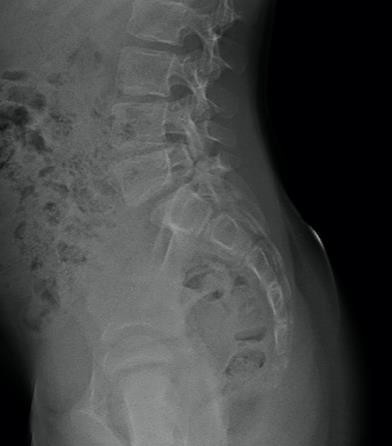

Radiographie d'un spondylolisthesis stable

Spondylolisthesis stable